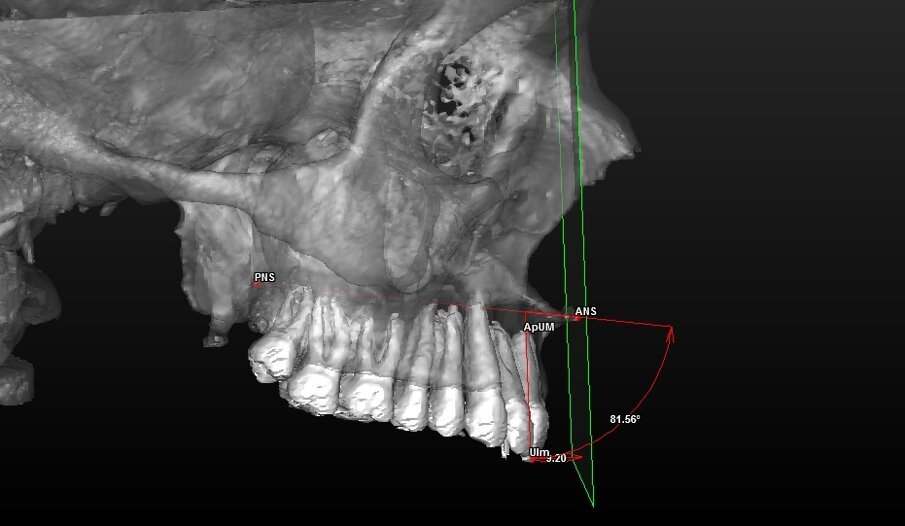

UIm: Punto mediano dei margini degli incisivi U11 e U21;Dai landmark dentali (U11, U21, ApU1R e ApU1L) sono stati ricavati due punti mediani calcolati direttamente dal software:

- ApUM: Punto mediano degli apici degli incisivi ApU1R e ApU1L.

Con questi è stato possibile tracciare una retta che passasse tra i punti UIm e ApUM e che possa essere considerato così il vero asse mediano degli incisivi centrali definendolo “Asse Incisale Superiore”.

Dai landmark ossei ANS e PNS è stata tracciata una retta passante per questi due punti definita “Asse Spinale”.

Componente dentale (Tab. 4) (Figg. 8, 9):

Angolo tra asse spinale e asse incisale |

Fig. 3_Ricostruzione 3D del mascellare superiore ed arcata dentaria con visione di profilo dei landmark utilizzati.

Fig. 9_Valutazione della componente dentale in visione di profilo.